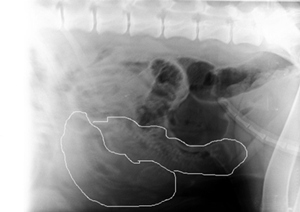

Da es laut Röntgenbild nur zwei Welpen waren, und es immer hohe Risiken

bei einer Kaiserschnitt OP geben kann, hat uns der TA dazu geraten,

durch strenge medizinische Versorgung, das Inara die zwei Welpen

natürlich zur Welt bringen soll.

Wären es mehr Welpen gewesen, wäre eine Normalgeburt nicht möglich

gewesen!

Auf den Bildern kann man sehr schön die Beiden Kleinen sehen.

Info: die schwarzen "Blasen" im oberen Bereich sind keine Welpen, es

ist Luft :-).